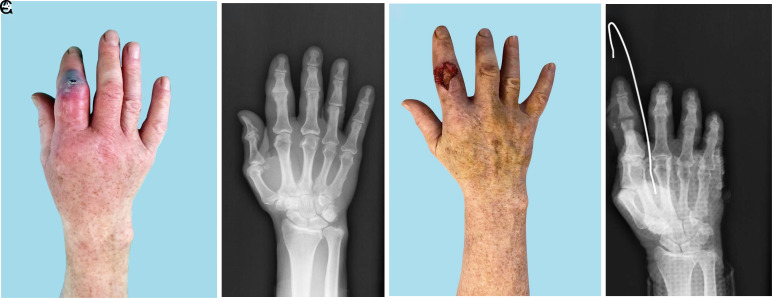

Objective: Septic arthritis of the hand often leads to sti!ness or even complete loss of joint function. Septic arthritis with osteomyelitis is especially severe. In this case, most experts recognize the need to perform arthrodesis. This study is devoted to another way of solving this problem.

Methods: The results of treatment of 240 patients (255 joints) treated for septic arthritis of the hand were retrospectively analyzed. In most cases, septic arthritis with osteomyelitis was noted-145 (56.9%). All patients were operated on. After resection of osteochondral structures, in most cases, the developed method named distraction (gap) arthroplasty was used. Mid-term results were assessed within 7 months (interquartile range [IQR]: 4-9). Finger function was assessed using the total active motion (TAM) system.

Results: With the development of osteomyelitis, the delay in treatment was longer than in patients without osteomyelitis: 13 days (IQR: 4-22). Tendon destruction, which prevents the restoration of joint function, was observed in 12 (4.7%) cases. After rehabilitation, the maximum median TAM was in patients after arthritis with osteomyelitis of the metacarpophalangeal (MCP) joint-68.1% (IQR: 50.1-86.2), 65.3% (IQR: 49.4-75.4), 60.8% (IQR: 58.7-72.4), and 63.8% (IQR: 51.7-71.9) after arthritis with osteomyelitis of the proximal interphalangeal (PIP) joint, distal interphalangeal (DIP) joint, and thumb interphalangeal (IP) joint, respectively.

Conclusion: Septic arthritis of the hand is a severe disease that is often accompanied by the development of osteomyelitis, the spread of a purulent process to the paraarticular soft tissues, and sometimes the destruction of the tendons. It often leads to the need for arthrodesis or amputation of the finger. As an alternative to this, a treatment method named "distraction (gap) arthroplasty" after resection of the a!ected structures of the joint can be considered.